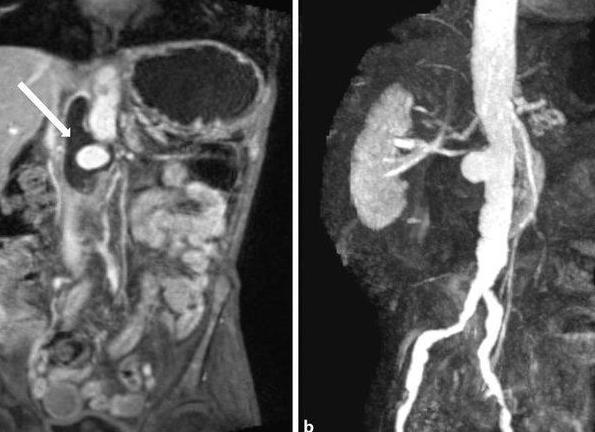

Внутривенное введение гадолиния помогает облегчить диагностику тяжелых клинических случаев

Когда требуется качественная визуализация опухолевых очагов, участков с нарушением кровообращения (ишемии), воспалительных и фиброзных процессов, назначается МРТ с контрастом. Внутренние органы, расположенные в брюшной полости, в большинстве ситуаций исследуют таким способом. При этом вводится внутривенно один из препаратов, созданных на основе солей гадолиния, таких как Гадовист, Магневист, Омнискан и другие.

При попадании контраста в кровеносные сосуды, происходит их окрашивание и накопление в различных тканях органов. При этом скорость накопления и выведения вещества напрямую зависят от тканевого кровоснабжения и интенсивности метаболизма. Перед такой процедурой обязательно проводится тест на чувствительность пациента к используемому препарату во избежание появления аллергических реакций. Введение контрастного вещества противопоказано пациентам с почечной недостаточностью, а также беременным и кормящим женщинам.